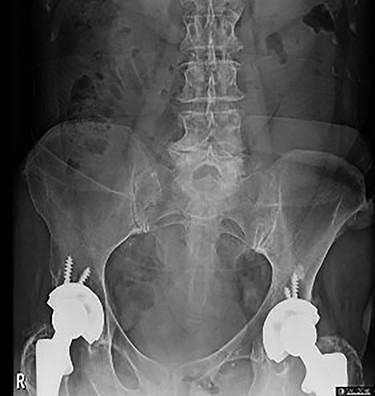

On initial presentation, her blood results were as follows: white cell count (WCC) 14.8 × 109 cells/l (RR 4.3–11.2 cells/l), neutrophils 12.3 × 109 cells/l (RR 2.1–7.4 cells/l) and C-reactive protein (CRP) 1.9 mg/l (RR 0–5 mg/l). Imaging performed included an abdominal film, which showed nonspecific bowel gas pattern (Fig. 1). The patient was managed conservatively and discharged home. She represented 2 days later with worsening symptoms and blood results of WCC 20.1, neutrophils 18.4 and CRP 6. She was admitted under the surgical team and a thoracic and abdominal CT scan was done (Figs 2–4). It was initially reported as significant dilated small bowel loops in keeping with small bowel obstruction due to a femoral hernia. However, the scan was revisited by the surgical team in more detail as the images appeared to represent an obturator hernia. Upon further discussion, these findings were corroborated by the radiologist and a strangulated left obturator hernia was identified.

Axial section demonstrating small bowel loops in left obturator space.